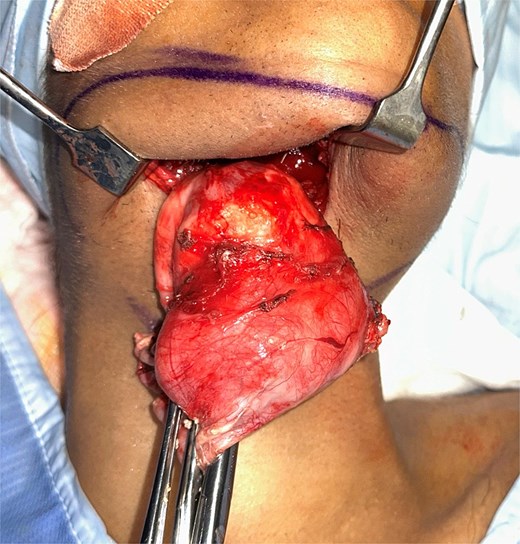

Given the size and symptomatic burden, the patient underwent excision of the mass via a midline transcervical approach. Dissection proceeded through skin and cervical fascia to the anterior bellies of the digastric muscles, which were markedly displaced and adherent to the cyst capsule. After lateral retraction of these structures, the cyst was decompressed intraoperatively to facilitate its removal, releasing a large volume of keratinous debris. The cyst was dissected free from the mylohyoid and geniohyoid muscles and the submandibular gland (Fig. 4).

Histopathology revealed a 9 × 8 cm cyst lined by orthokeratinising squamous epithelium with evidence of ulceration, granulomatous reaction, fibrosis, and cyst wall thickening—confirming a giant epidermoid cyst. No features of a foregut duplication cyst were identified. The patient remains recurrence-free at follow-up (Fig. 5).